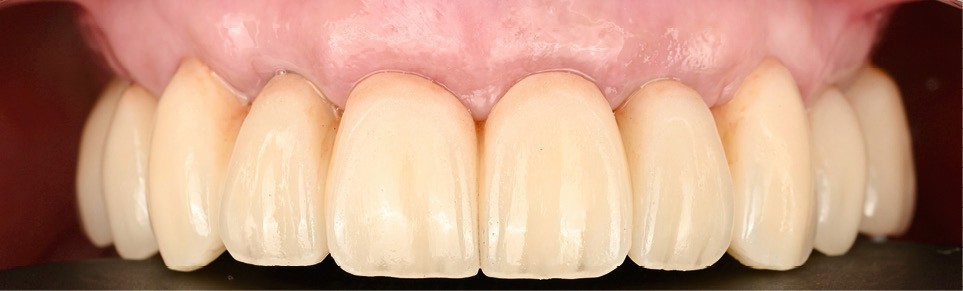

Elle est réalisée en zircone monolithique usinée puis stratifiée manuellement (fig. 9). Dans cette approche hybride numérique-analogique, la CFAO assure la précision de la structure, tandis que la stratification manuelle apporte la personnalisation esthétique et la vitalité du rendu [4]. Le résultat illustre la convergence entre précision technologique et sensibilité clinique (fig. 10).